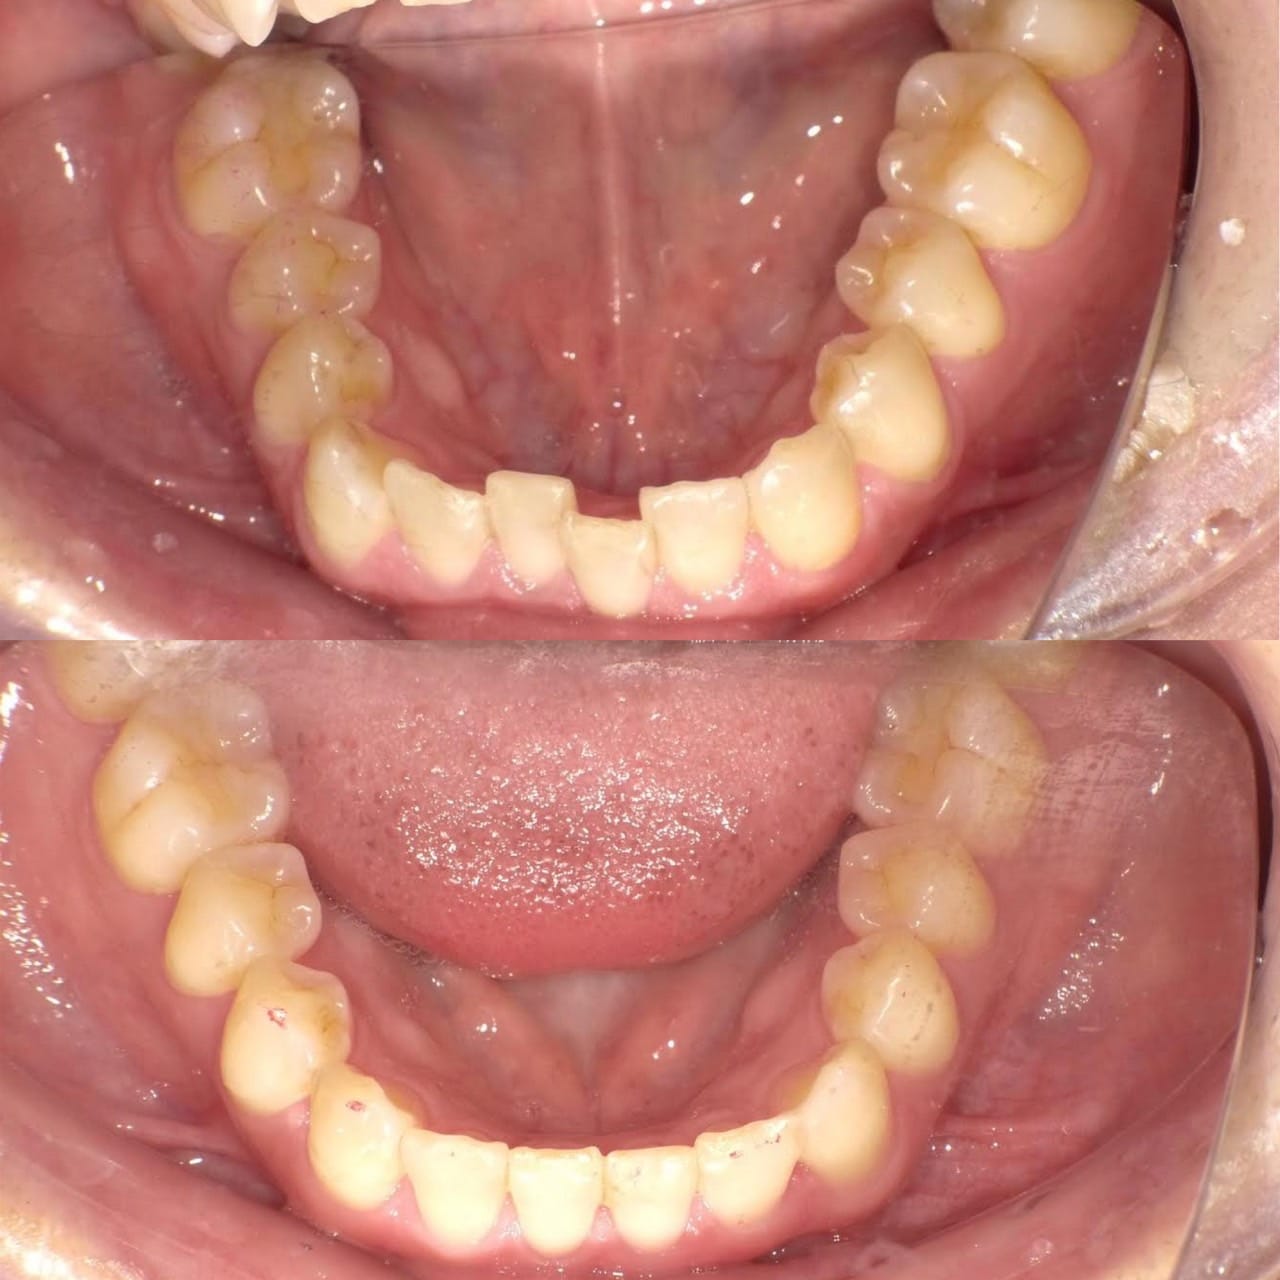

歯が欠けていて、隙間がある。

歯並びが気になる。

亀裂が入っている。

歯の無いところがある。

見える銀歯が気になる。

綺麗な口元になりたい。

という患者様の診療です。

上はジルコニアセラミックでかけているところを修復しながら、綺麗な歯並びで、患者様のお好きな白い歯に。

下の歯の無い所にはインプラント。

見える銀歯は外して綺麗な歯に修復。

また、ホワイトニングをして上の歯との色のギャップを少なくして、明るい口元にしました。